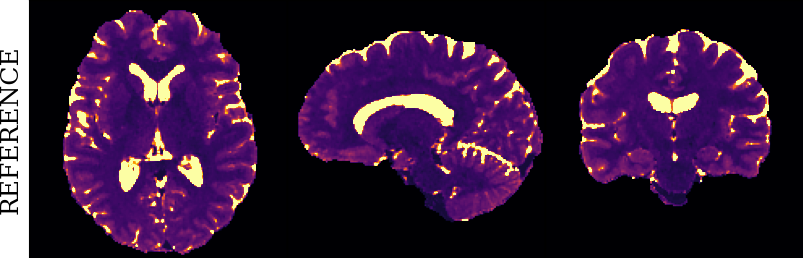

To monitor performance progress, we mapped TSMI to Q-Maps every five epochs. To mitigate the lengthy processing times associated with Dictionary Matching, we implemented a fully connected network to directly map TSMI to Q-Maps [5], significantly reducing processing time. However, for the final assessment, we employed DM on all techniques at the conclusion of the training process (epoch 500). We report in Table 1 the Mean Average Percentage Error (MAPE) of T1/T2 maps, and Peak Signal-to-Noise Ratio (PSNR) and Structural Similarity (SSIM) Index for T1/T2 and normalised PD. To accompany these metrics we also offer in Fig. 2 the reconstructed T1 and T2 maps for the different approaches.

The training and validation loss (Fig. 1) served as valuable guides for architecture and training design. To demonstrate this, we selected a subset of experiments in which we kept certain variables fixed and only modified the one under inspection. From Fig. 1 (a)-(d), MAPEs curves show there is a clear setting with the preferred performance. Specifically, from Fig. 1a, it is evident that using DRUNet yields a clear improvement over the original architecture. This could be attributed to the utilisation of residual units in addition to other architecture differences, such as the choice of upsampling operator (transpose convolution for DRUNet and trilinear for DIP). The choice of input (Fig. 1b) demonstrated a consistent pattern among the tested options, with low rank (conjugate gradient) initialiser marginally outperforming the others. Fig. 1cshows that by epoch 100, stochastic approaches exhibit lower reconstruction errors compared to non-stochastic methods. For example, adaptive LR with stochastic training yields a combined MAPE of 61.40% (17.09% T1 and 44.31% T2) vs. 213.69% (35.50% T1 and 178.19% T2) for the non-stochastic method. This fast convergence is due to adaptive LR and stochastic updates across coils. Despite similar execution times ( 34 min for stochastic with adaptive LR vs. 32 min for non-stochastic with fixed LR), the rapid error reduction makes StoDIP more attractive for training.. To assess the early stopping of DIP models, a key element, we present Fig. 1d. The original work by Ulyanov et al. [21] used 2k iterations, while Hamilton et al. [12] used 30k. In contrast, our settings show StoDIP achieving competitive performance in under 500 epochs (4k iterations) on the entire volume. However, StoDIP can overfit to k-space measurements, affecting reconstruction accuracy, and thus the iteration at which it stops could have a greater impact. We show that adding a spatial penalty term addresses overfitting and instabilities. This is supported by the maps in Fig.2, supplementary material Figures 1-3, and metrics in Table 1. StoDIP reconstructions lack aliasing artifacts, and the TV regularizer (StoDIP + TV) further improves Q-Map reconstruction by reducing checkerboard artifacts observed in StoDIP outputs alone.